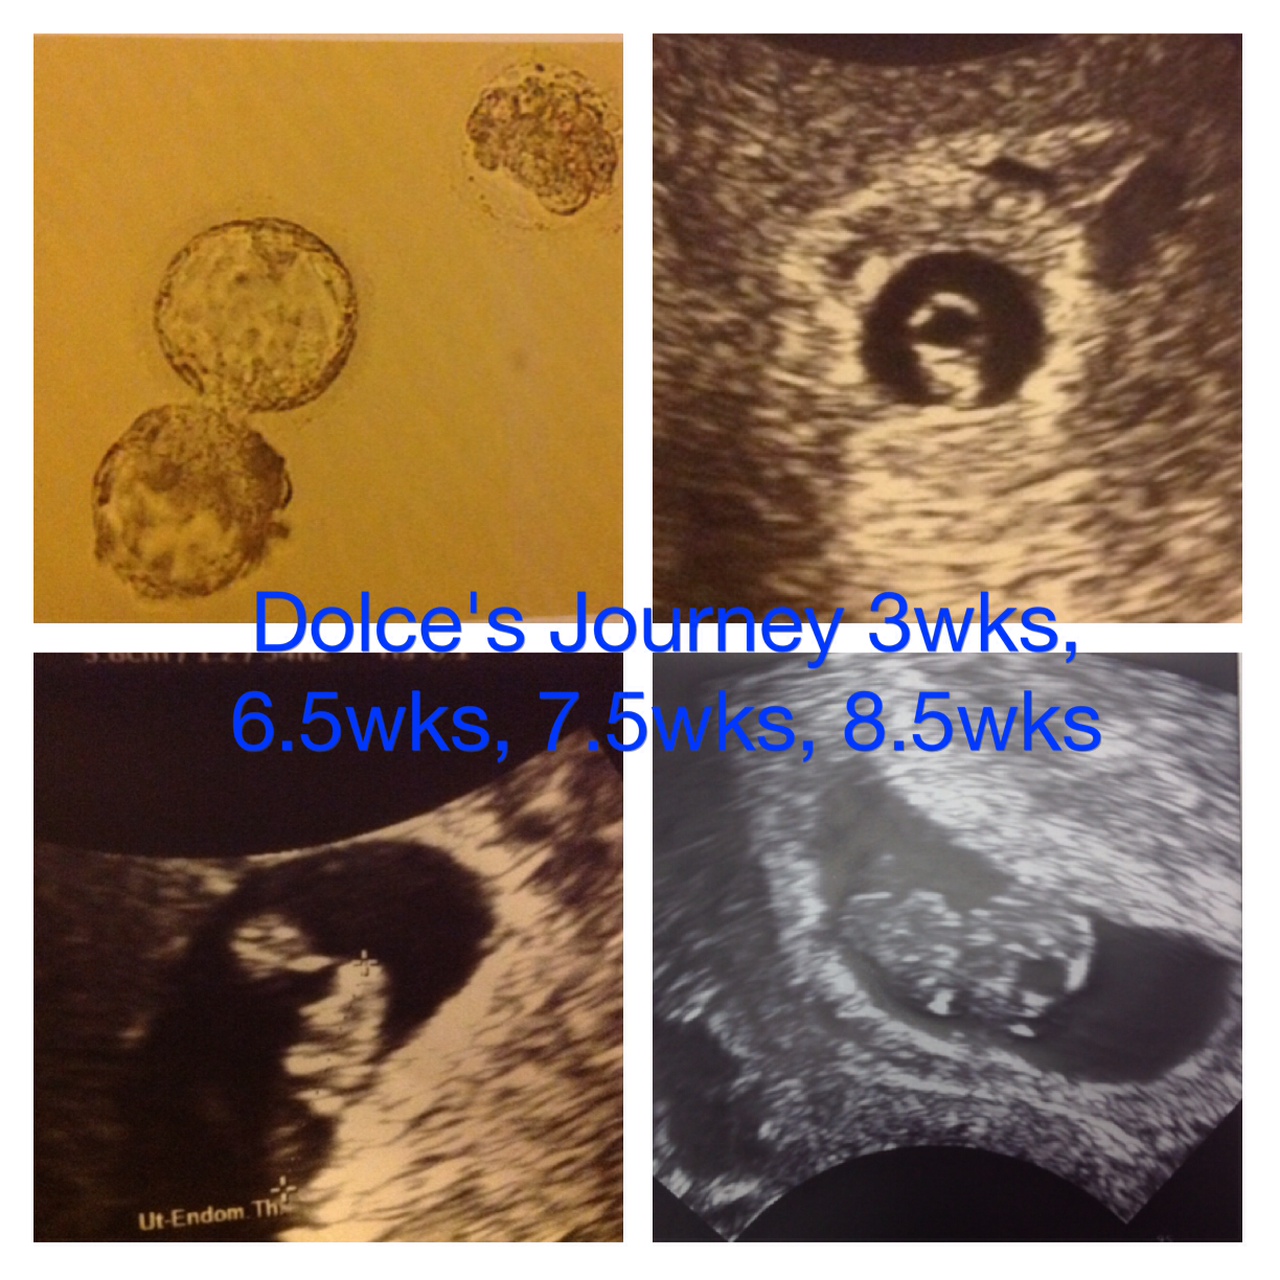

IVF#1 - BFP 6/18/13 - Tommy born sleeping 10/1/13

IVF#2 - BFN

IVF#3 - BFP 6/5/14 EDD 2/14/15 TWIN BOYS - MATTHEW AND TIMOTHY ARRIVE 12/2/14

Beta #1 12dpo - 164 & progesterone - 89!, Beta #2 16 dpo - 1189, 5w3d - u/s shows TWINS!

6/19- u/s showed heartbeats! Baby A 111 & Baby B 118, both measuring 6w1d

7/3- Baby A hb 170, Baby B hb 166 - both measuring perfect.

7/18 - Baby A 165, Baby B 171 - both measuring right on track & moving all around!